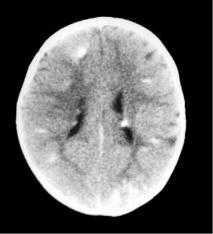

Наиболее типичными нарушениями в головном мозге являются корковые туберсы и субэпендимарные узлы. Туберсы могут быть как единичными, так и множественными, располагаются в виде выступов над единичной или прилегающими бороздами коры, расширяя их. Субэпендимарные узлы локализуются в стенках боковых желудочков и, реже, в стенках III и IV желудочков мозга. У новорожденных субэпендимарные узлы редко бывают кальцифицированными. По мере роста ребенка наблюдается постепенное отложение кальция в субэпендимарных узлах.

Субэпендимарные узлы в 10% случаев трансформируются в гиганто-клеточную астроцитому, которые манифестируют обычно между 5 и 10 годами жизни, имеют тенденцию к росту и локализуются у отверстия Монро

Субэпендимарные кальцификаты и корковые туберсы на КТ головного мозга ребенка с туберозным склерозом

Субэпиндемальные узлы и корковые туберсы на МРТ

КТ головного мозга при туберозном склерозе. Видны кальцинированные субэпендимальные узелки в стенках боковых желудочков.